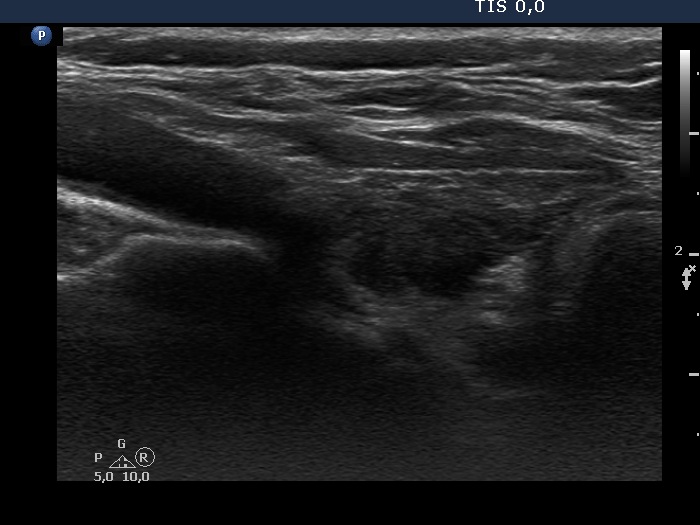

Consecutive patients with the final diagnosis of Hashimoto's thyroiditis - case 41 (133) (ultrasonographic picture 5)

Left lobe, longitudinal view. The hypoechogenic areas correspond to more active foci of thyroiditis.